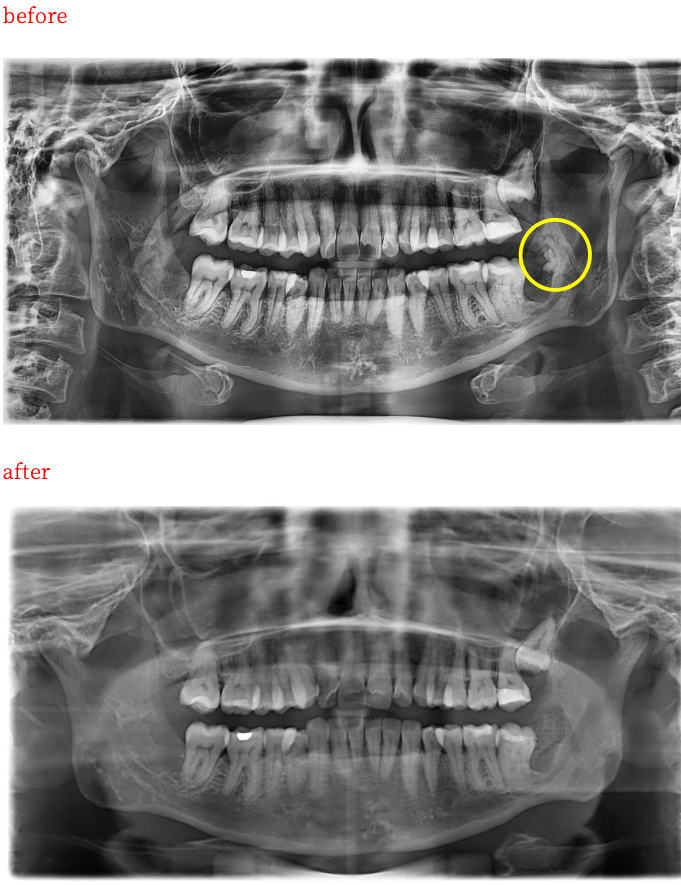

在確認她確實希望把問題一次解決之後,我才進一步向她說明拍攝電腦斷層(CBCT)的必要性,並解釋為什麼必須透過影像準確評估殘留斷根的位置,以及它與下齒槽神經等重要解剖結構的相對關係。

這樣的評估,能讓我們在手術前先規劃最佳處置方式,並在實際手術過程中避免傷及重要的組織結構,降低神經受損與術後併發症的風險。

在舒眠麻醉的輔助下,我順利完整處理先前未能拔除的斷根,並同步進行大範圍補骨,為後續癒合與長期穩定性打下基礎。